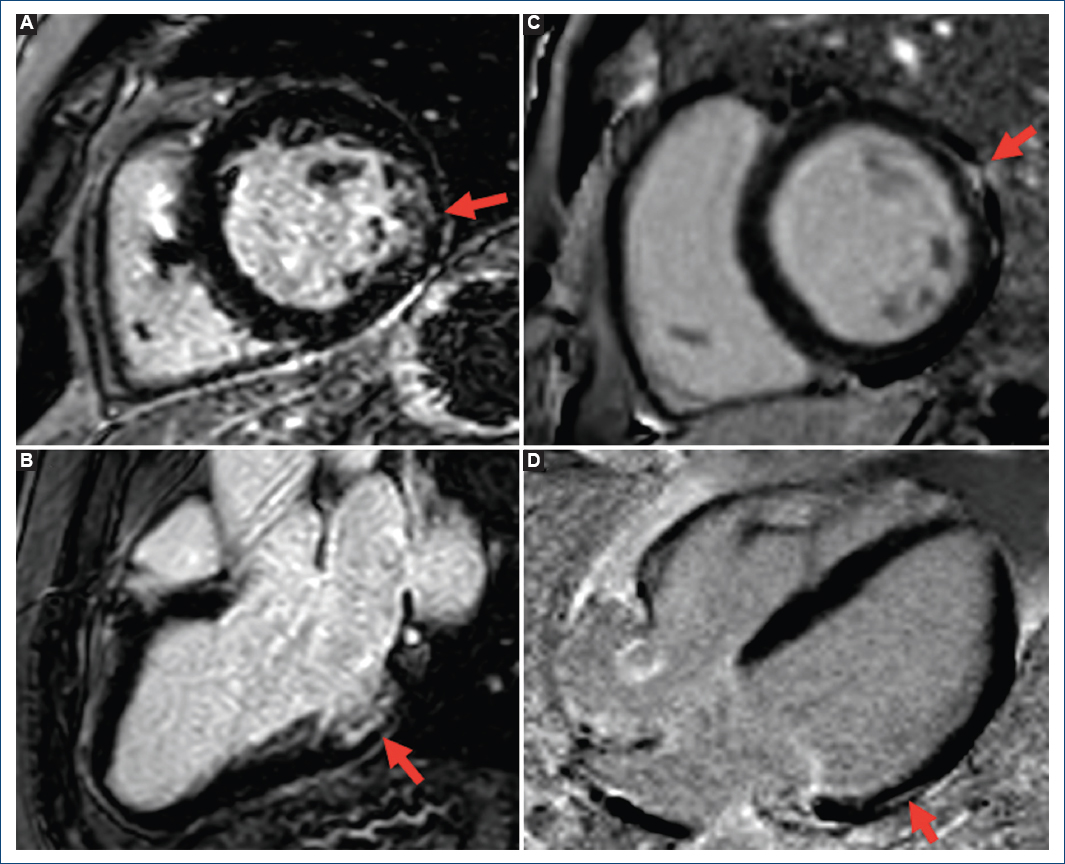

Figura 1 A y B: resonancia magnética (RM) del caso índice, secuencias de realce tardío de gadolinio (RTG), eje corto y eje largo, que muestra fibrosis subendocárdica del 60% inferolateral. C y D: resonancia magnética de la madre del caso índice, secuencias de realce tardío de gadolinio, eje corto y eje largo, que muestra fibrosis lineal intramiocárdica lateral basal.

El caso índice era un varón de 44 años, sin antecedes de interés, que ingresó por un síncope de perfil cardiogénico. En el electrocardiograma (ECG) se observó un bloqueo de rama izquierda, por lo que se realizó un estudio electrofisiológico que mostró un trastorno de la conducción intrahisiano con un AH de 100 ms y un HV de 61 ms. Se decidió el implante de un marcapasos bicameral. Presentaba el ventrículo izquierdo no dilatado con función sistólica (fracción de eyección del ventrículo izquierdo [FEVI]) levemente reducida (48%), que se interpretó como probablemente secundaria a la asincronía intraventricular. No se observaron valvulopatías funcionalmente relevantes ni datos de hipertensión pulmonar significativa. El estudio etiológico se completó con una resonancia magnética (RM) cardiaca realizada a los 3 meses, que mostró un ventrículo izquierdo de dimensiones en el límite superior de la normalidad (volumen telediastólico 99 ml/m2) con FEVI del 43% y un foco de edema inferolateral con fibrosis subendocárdica del 60% en dicho segmento (Fig. 1A y B). Una tomografía computarizada coronaria descartó la presencia de estenosis significativas. Se inició tratamiento neurohormonal, a pesar de lo cual al año desarrolló disfunción grave del ventrículo izquierdo, persistiendo asintomático. En la interrogación del dispositivo, el porcentaje de estimulación era inferior al 10% y se objetivaron varias salvas de taquicardia ventricular no sostenida de hasta ocho complejos, por lo que ante la presencia de disfunción ventricular grave y fibrosis se decidió realizar un up-grade a un desfribrilador automático implantable - terapia de resincronización cardíaca (DAI-TRC), con posterior recuperación completa de la FEVI.

En la evaluación inicial se elaboró un árbol familiar y se realizó un cribado en los familiares de primer grado (Fig. 2). Su madre había sido estudiada a los 60 años por síncopes de perfil cardiogénico con hallazgo de bloqueo de rama izquierda, objetivándose posteriormente en un estudio electrofisiológico un trastorno de la conducción infrahisiano y se le implantó un marcapasos. Desde el punto de vista estructural presentaba un ventrículo izquierdo no dilatado con FEVI del 50% y en la RM realizada 2 años después del implante del marcapasos se observó una FEVI del 46% con acinesia limitada al segmento medio lateral, sin observarse fibrosis. Por otro lado, su hermano había sido estudiado previamente por extrasistolia ventricular de baja densidad sintomática con un bloqueo de rama derecha en el ECG. Estructuralmente presentaba un ventrículo izquierdo ligeramente dilatado con FEVI normal y un foco de fibrosis lineal intramiocárdica lateral basal en la RM (Fig. 1 C y D). El abuelo materno era portador también de marcapasos desde los 52 años por un bloqueo auriculoventricular completo y había fallecido en la octava década de la vida por insuficiencia cardíaca.